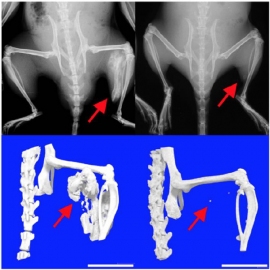

マウスでの異所性骨形成の様子。矢印の付近にアクチビンの刺激を与えた。(写真: 京都大学の発表資料より)[写真拡大]

FOPは、全身の筋肉や腱、靭帯などが徐々に骨へと変化していく進行性の病気で、発症の割合は200万人に1人、患者は日本全国に約80名存在する。ラパマイシンにはその骨への変化を抑える効果があると、研究で判明した。